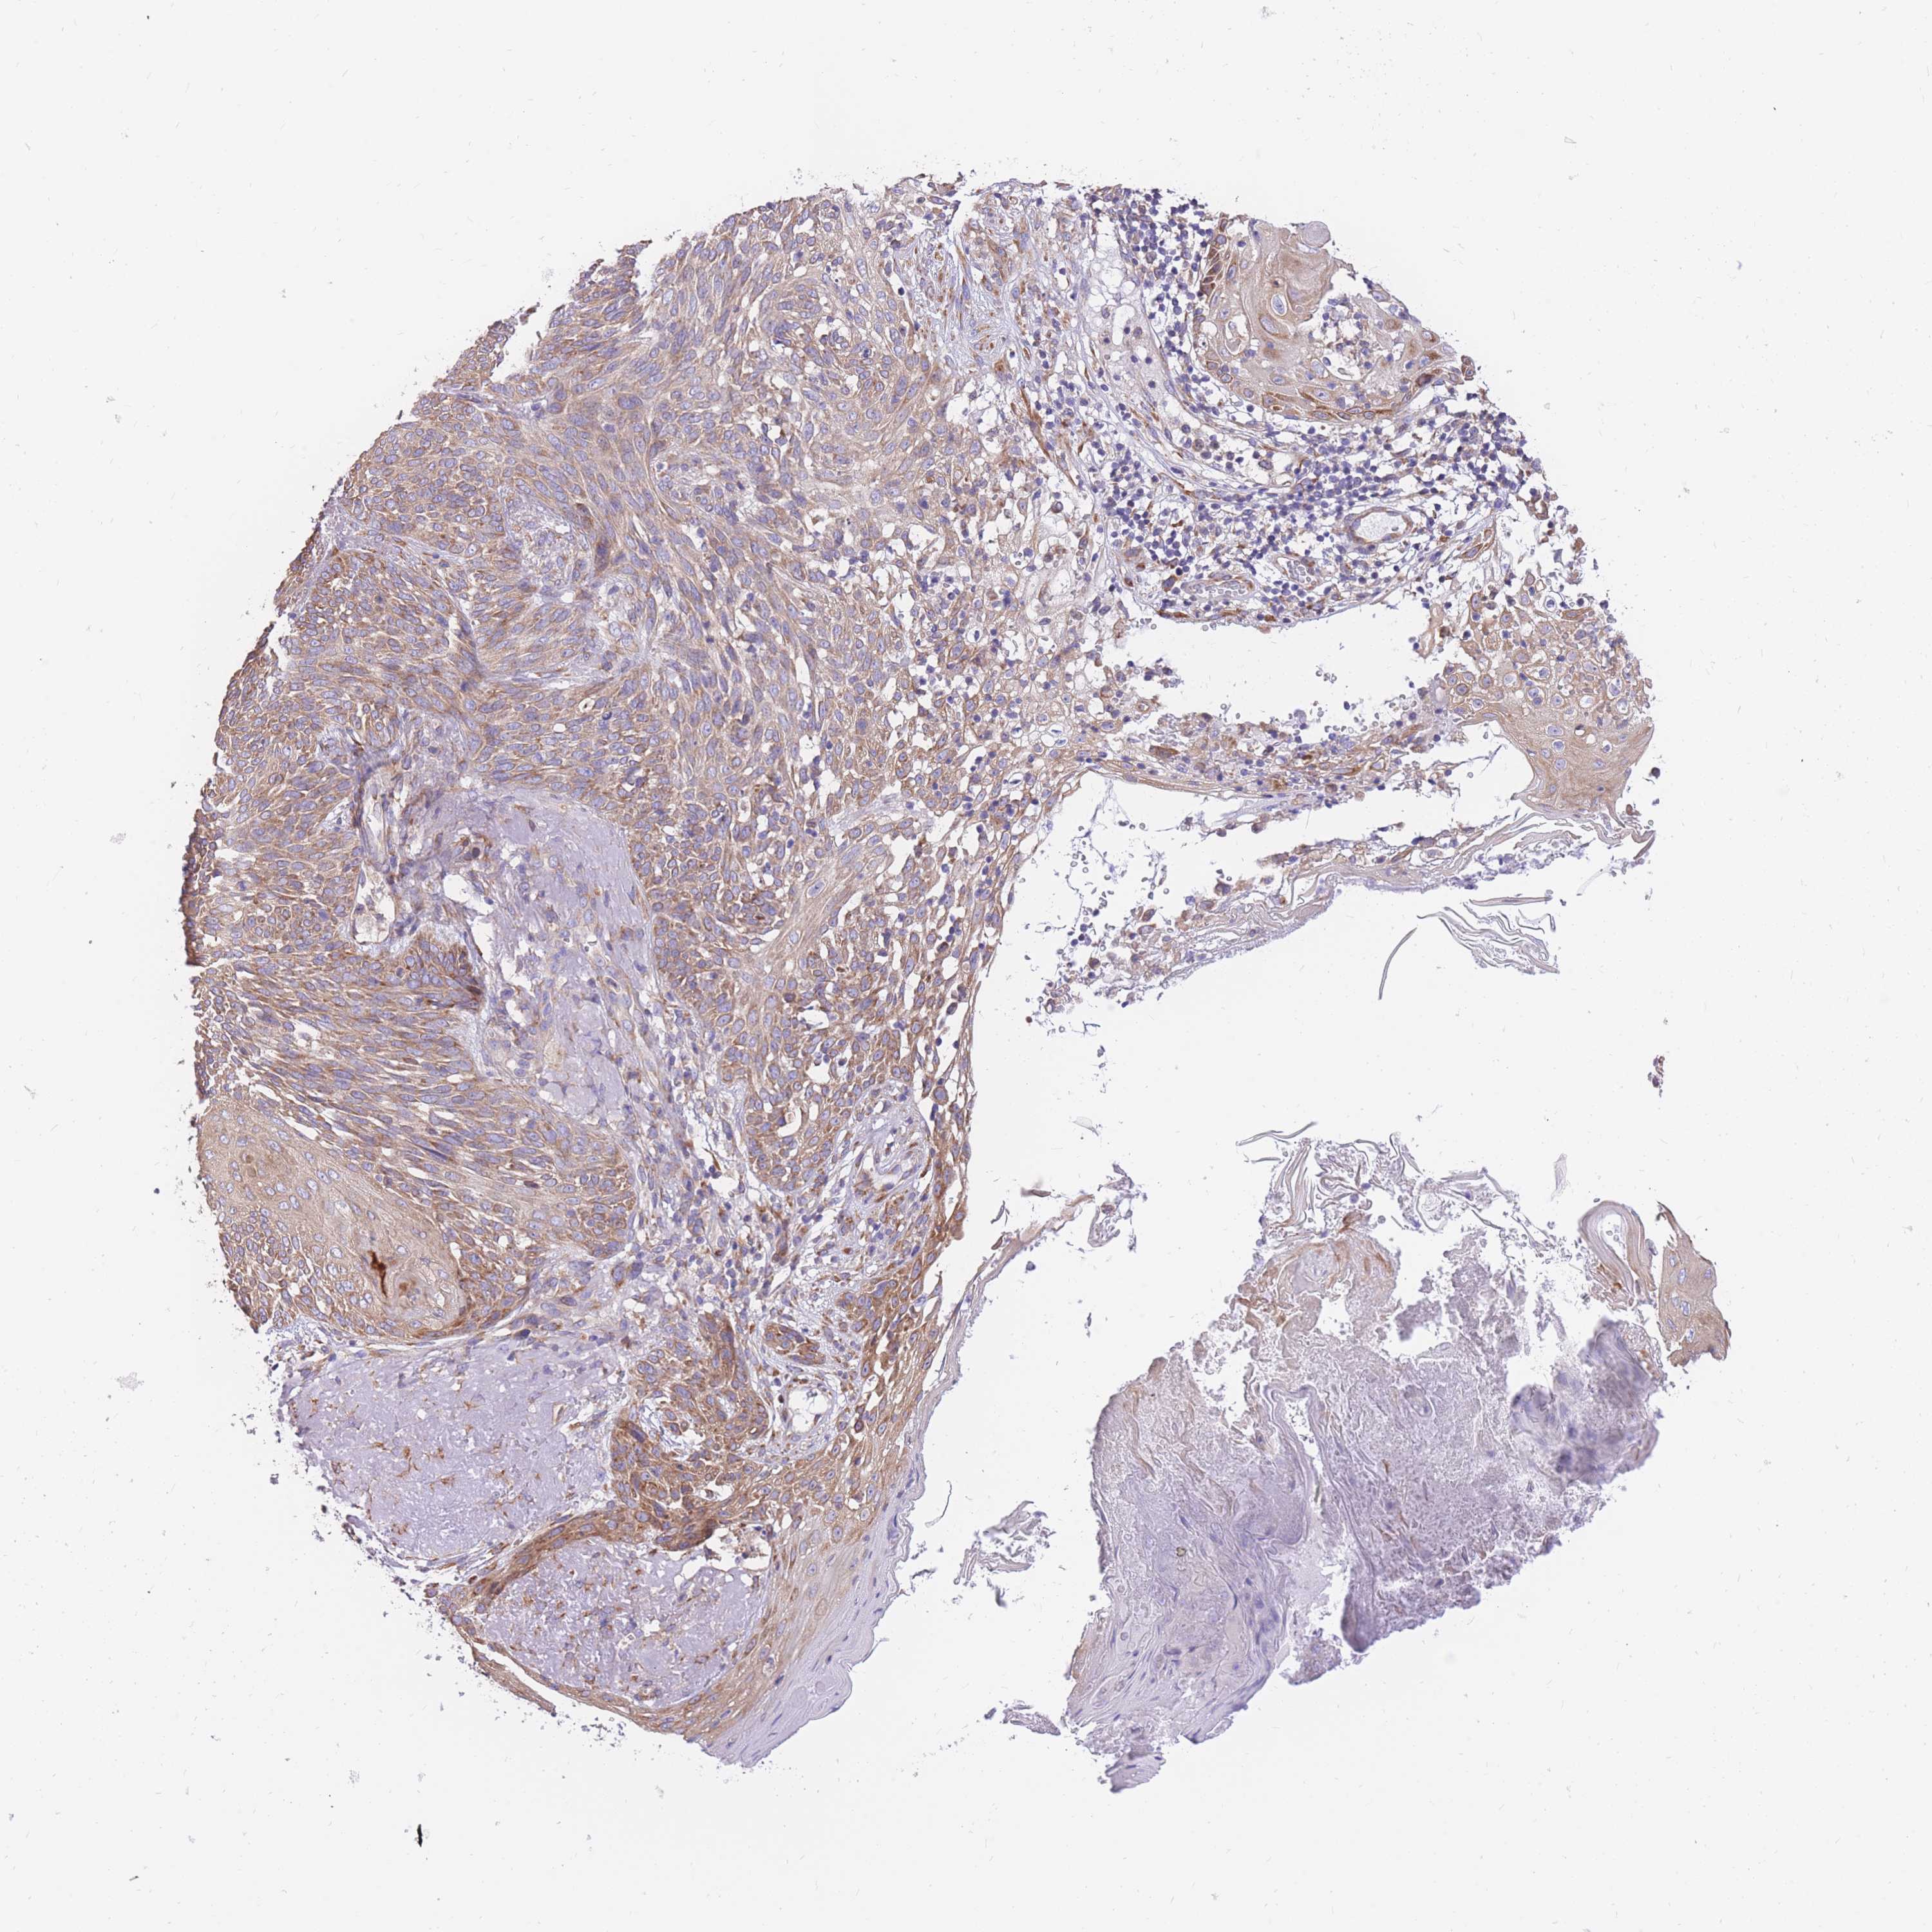

SKIN CANCER - Protein expressioni

A mouse-over function shows sample information and annotation data. Click on an image to view it in a full screen mode. Samples can be filtered based on level of antibody staining by selecting one or several of the following categories: high, medium, low and not detected. The assay and annotation is described here.

Antibody stainingi

Antibody staining in the annotated cell types in the current human tissue is reported as not detected, low, medium, or high, based on conventional immunohistochemistry profiling in selected tissues. This score is based on the combination of the staining intensity and fraction of stained cells.

Each image is clickable and will lead to virtual microscopy that enables deeper exploration of all samples and also displays staining intensity scores, fraction scores and subcellular localization as well as patient and tissue information for each sample.

Antibody HPA051245

Staining

High

Medium

Low

Not detected

Intensity

Strong

Moderate

Weak

Negative

Quantity

>75%

75%-25%

<25%

None

Location

Nuclear

Cytoplasmic/membranous

Cytoplasmic/membranous,nuclear

Basal cell carcinoma

Squamous cell carcinoma, NOS

Squamous cell carcinoma, metastatic, NOS

Squamous cell carcinoma in situ, NOS